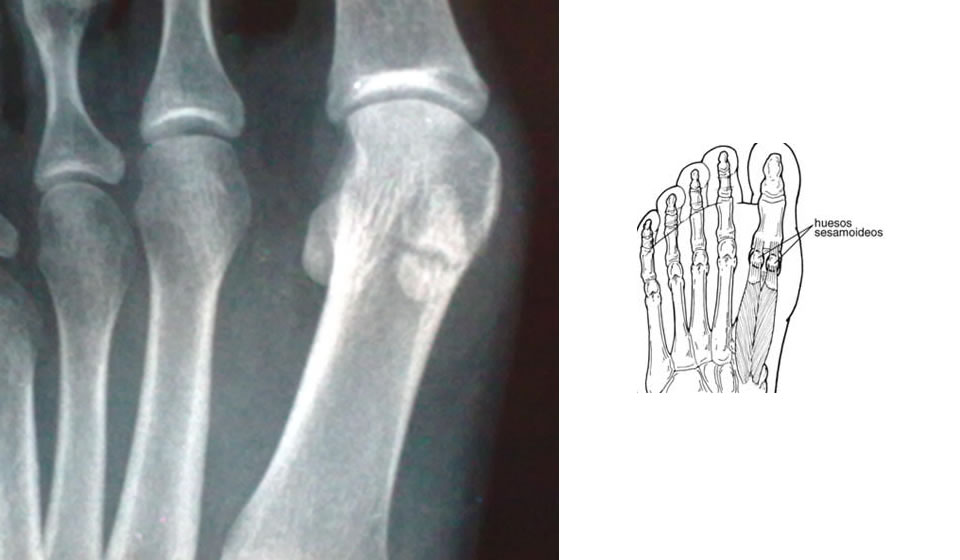

5- Infección de los Sesamoideos:

No es común, pero se la puede ver en diabéticos con úlceras tróficas debajo del primer metatarsiano. A veces se presenta luego de heridas punzantes del pie y luego de la práctica de infiltraciones en la articulación MTF. (primero se afecta la articulación MTF y luego el sesamoideo).

Otras veces se producen osteomielitis por vía hematógena.

El exámen físico revela una articulación MTF caliente, tumefacta y dolorosa.

Deben tomarse muestras bacteriológicas para cultivo y antibiograma y realizar un debridamiento quirúrgico amplio de la articulación y el sesamoideo que a veces debe ser resecado. Deben extremarse cuidados especiales para el diabético para evitar dichos procesos ( plantillas, calzado)

La Rx simple suele ser suficiente como elemento auxiliar del diagnóstico y en diferentes casos nos valemos de diferentes test semiológicos y otros estudios complementarios (centellograma, TAC, RNM, etc)